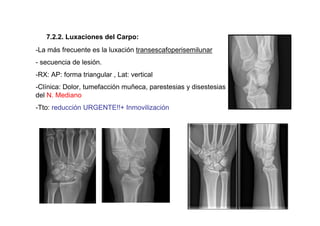

7.2.2. Luxaciones del Carpo:

-La más frecuente es la luxación transescafoperisemilunar

- secuencia de lesión.

-RX: AP: forma triangular , Lat: vertical

-Clínica: Dolor, tumefacción muñeca, parestesias y disestesias

del N. Mediano

-Tto: reducción URGENTE!!+ Inmovilización